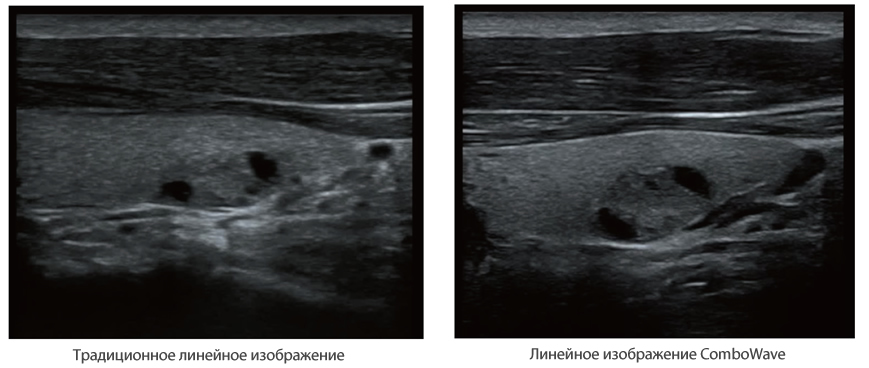

Совместно с современными ультразвуковыми технологиями новое решение от Mindray преобразует актуальные задачи клиентов в клинические потребности. Постоянно развиваясь, эта система сочетает в себе стремление к неограниченным возможностям и желание заглянуть в будущее.

Многофункциональная система DC-60 Exp с X-Insight представляет собой комплексное решение, которое помогает управлять повседневной клинической практикой с легкостью и уверенностью.

Основываясь на глубоком понимании потребностей клиентов, компания Mindray разработала систему DC-60 Exp с X-Insight, чтобы обеспечить высокую производительность и точность визуализации вкупе с наглядностью, исключительной интеллектуальностью и огромным опытом.